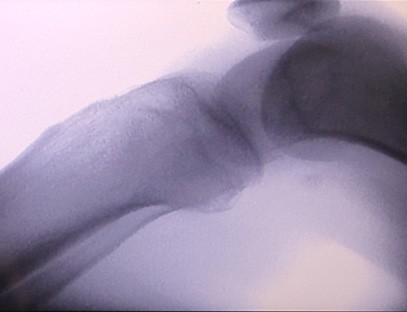

Una máquina de rayos X portátiles un instrumento portátil de baja dosis de radiación, muy seguro, que puede obtener imágenes de alta calidad al tiempo que reduce la exposición a la radiación. Compensa las deficiencias de los grandes equipos hospitalarios y se puede mover y transportar en cualquier momento. Especialmente adecuado para unidades e individuos con presupuesto insuficiente y bajos requisitos de imágenes. Nuestra máquina de rayos X de nueva generación está equipada con una pantalla grande de alta definición de 10 pulgadas, que tiene un rango de ángulo de visión más amplio y puede ver completamente a través de toda la palma, incluidas fracturas, dislocaciones, artritis y tumores óseos. Se puede conectar a una impresora de películas para imprimir películas ortopédicas y también se puede utilizar para producción y pruebas industriales. No necesita un cuarto oscuro, perspectiva directa, observación en tiempo real. Esta máquina tiene un sistema de imágenes de alta resolución que puede capturar imágenes de cualquier estructura ósea con mucha claridad. Proporcionar los mejores equipos y soluciones de prueba de rayos X para fabricantes de productos médicos, de mascotas, industriales, electrónicos, departamentos de inspección y mantenimiento y laboratorios de investigación.

Especialización:Diseñado para las necesidades de las clínicas ortopédicas, especialmente adecuado paraImágenes de rayos Xde extremidades como manos, muñecas, codos, hombros, rodillas, tobillos, etc.

Imágenes claras:Se utiliza tecnología avanzada de imágenes digitales para proporcionar imágenes de rayos X de alta calidad, lo que ayuda a los médicos a diagnosticar la afección con precisión.